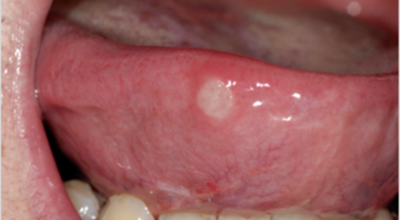

입안 점막이 동그랗게 패여 통증을 유발한다면, 아프타성 구내염을 의심할 수 있어요. 음식을 먹을 때마다 아픈 작은 궤양이 생겼다면, 아프타성 구내염을 의심할 수 있답니다. 아프타성 구내염은 빨간색 둘레를 가진 둥근 형태의 흰색 궤양이, 얕은 깊이로 한 개 및 여러 개 생기며 통증을 동반하는 것이 특징입니다. 전 인구의 20~40%가 발병할만큼 통상적으로 나타나는 질환으로 20대, 주로 여성들에게 많이 나타나며, 일주일 정도면 자연적으로 치유되지만 1~3개월 간격으로 빈번히 재발하는 것이 특징입니다.

원인은 입 속 점막의 작은 상처나, 바이러스, 세균의 감염, 특히 수면 부족이나 과로, 스트레스가 쌓여서 면역력이 떨어졌을 때와, 비타민 B12 또는 엽산 결핍 시에 많이 생기 다고 알려져 있답니다. 흔한 질환이니만큼 자연적으로 치유 되지만, 통증을 동반하고, 궤양의 크기가 커지거나 숫자가 늘어나기도 하기 때문에 연고나 외용제, 가글액 등을 활용해서 증상을 경감시키는 치료를 하기도 해요.